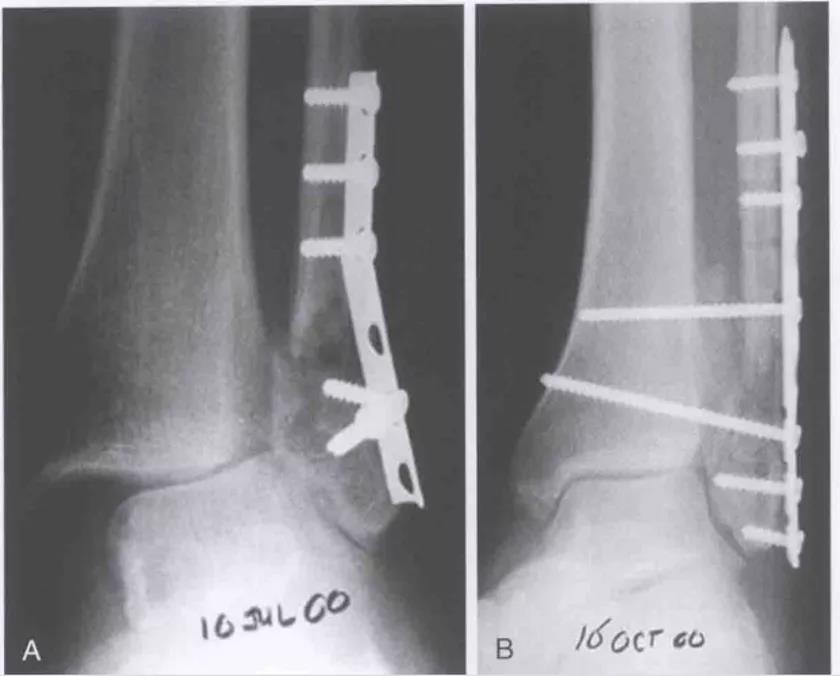

术前DR

术中:

失败病例:

术后2个月: